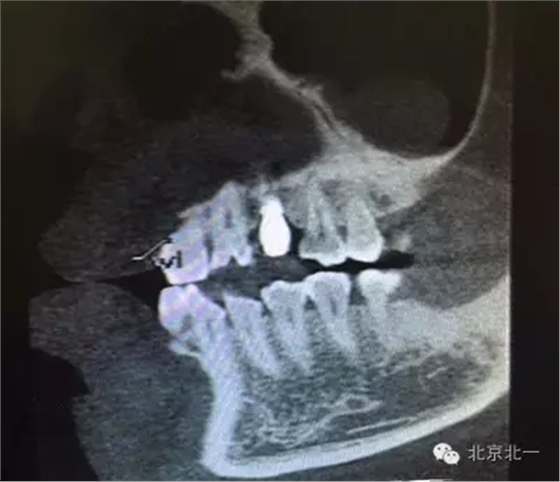

患者種植一月后種植區(qū)不適,偶有疼痛來(lái)院拍片發(fā)現(xiàn)23埋伏牙,與種植體相鄰,如圖一、二、三、四所示。

本病例建議:北一種植王明老師建議拔除埋伏牙,并同期植骨,觀察植體情況。提前告知患者失敗等風(fēng)險(xiǎn),簽署同意書。

但是國(guó)外文獻(xiàn)卻有不拔除埋伏牙的直接種植病例報(bào)告陳剛博士(本文獻(xiàn)由友睦齒科陳剛博士提供,向陳剛博士致謝。感興趣的醫(yī)生可去下載。)